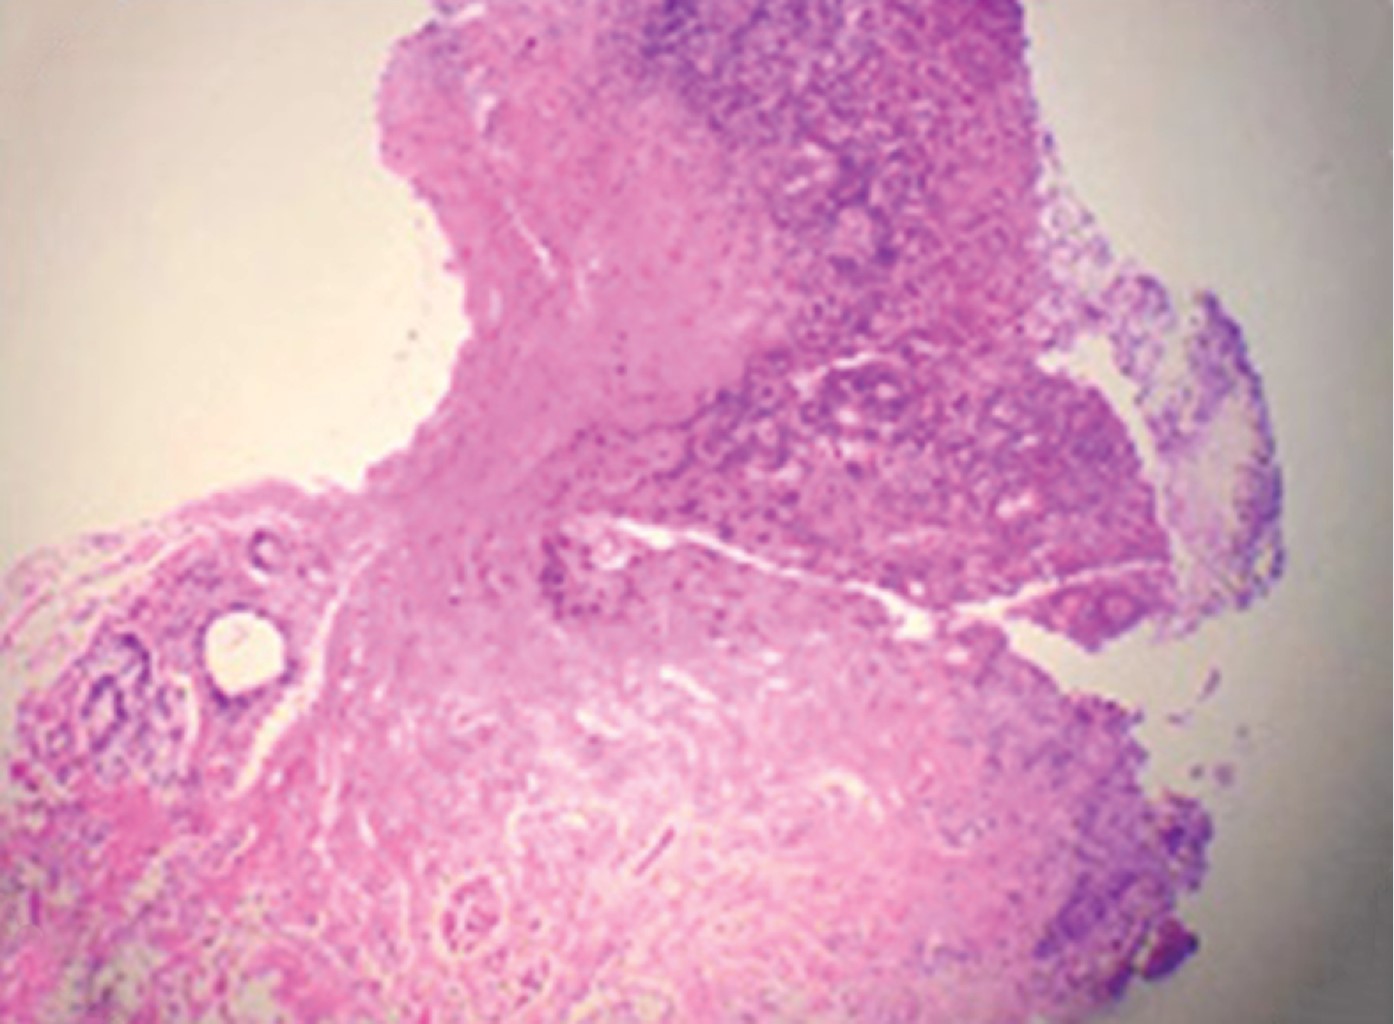

Clínicamente se presenta como una úlcera de 1 a 2 cm de diámetro con bordes indurados, asintomática o extremadamente dolorosa.12 Histológicamente se muestra la zona ulcerada de la mucosa, cubierta por exudado fibrinoide con detritus celulares. En la base de la úlcera hay tejido de granulación y los bordes epiteliales hiperplásicos; la submucosa se encuentra ocupada por un infiltrado difuso compuesto por abundantes eosinófilos, linfocitos, plasmocitos e histiocitos.13,14

A la exploración intraoral se identifica la presencia de dentición mixta, múltiples lesiones cariosas, mordida abierta posterior y gingivitis generalizada. En mucosa bucal izquierda se identifica un aumento de volumen ulcerado que se extiende de la mucosa labial al carrillo, de consistencia indurada, cubierto por una membrana de color amarillo-verdoso y base sésil, por lo cual se realiza abordaje por parte del departamento de cirugía maxilofacial (Figura 1B). Se decide realizar toma de biopsia incisional, obteniendo como resultado: úlcera eosinofílica (Figura 2). Se indica el uso de clorhexidina en gel al 0.20%. A los siete días de tratamiento se observó una notable mejoría y disminución en el tamaño y molestia de la lesión (Figura 1C).